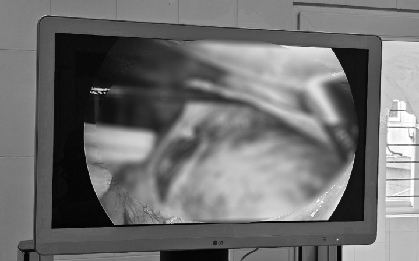

Đau tức hông lưng, nội soi người đàn ông thấy nhiều thứ này "bao vây, chèn ép" 2 quả thận

Thận phải bị nhiều thứ này "vây bám", cái lớn nhất có kích thước 12x9cm, trong khi, cái lớn nhất bên thận trái có kích thước 12,6x8,7cm.